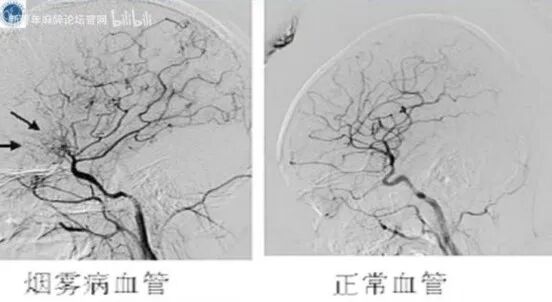

烟雾病又称脑底异常血管网病(MMD),是一组原发性双侧颈内动脉末端或其大分支血管进行性狭窄或闭塞,并且在颅底形成异常新生血管网为特征的慢性脑血管闭塞性疾病。此类疾病以脑缺血和脑出血为主要临床表现。